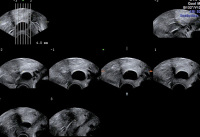

Tipps und Tricks im Gyn-Ultraschall: Ovula Nabothii – Die Eier des Martin Naboth. Wissenswertes zu einem Nebenbefund

Journal für Gynäkologische Endokrinologie 2016; 10 (1) (Ausgabe für Österreich): 12-14 Journal für Gynäkologische Endokrinologie 2016; 10 (1) (Ausgabe für Schweiz): 12-14 Volltext (PDF) Abbildungen